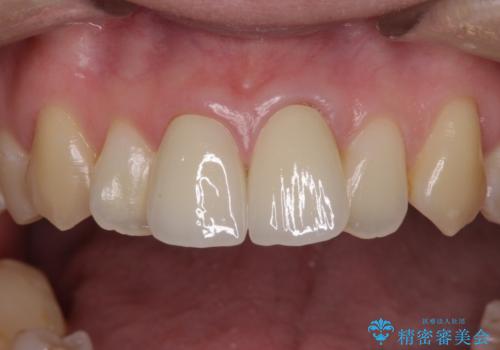

変色とともに、捻れていたことも気になっていたので、その両方を解決させることとしました。

2本同時に処置したことで、形や色調をそろえることができ、自然な口元になりました。